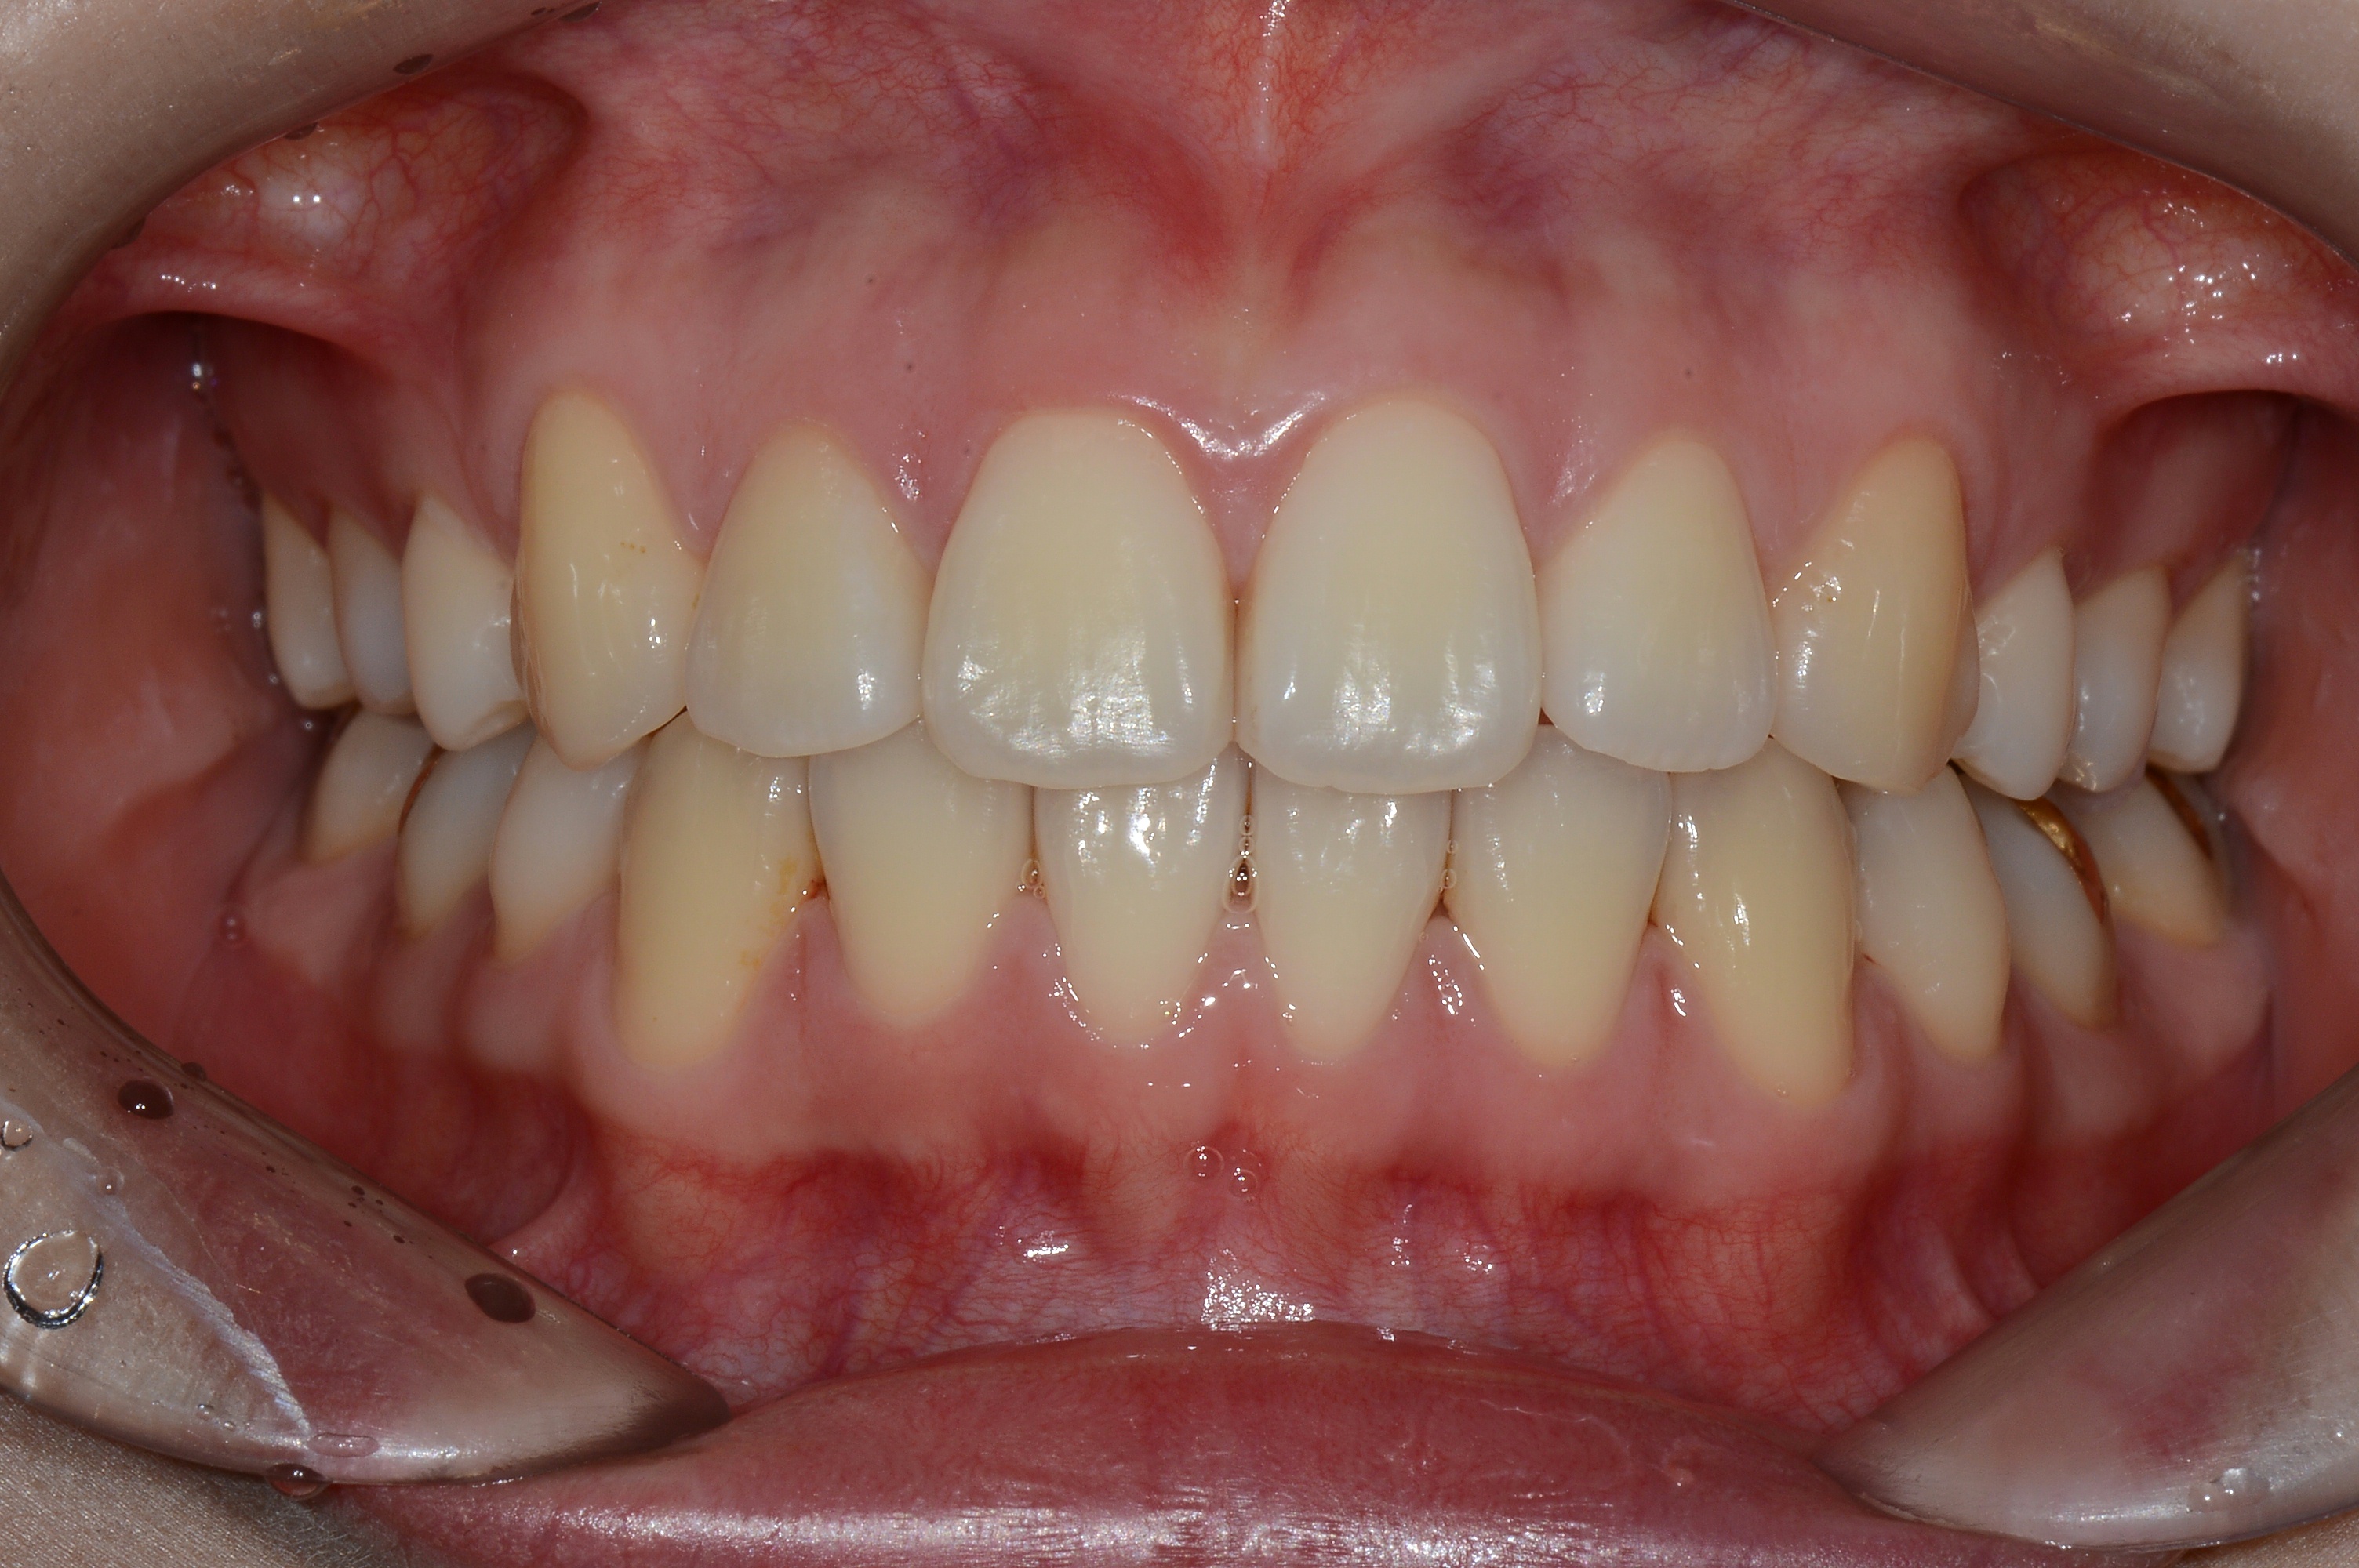

치료 후 사진입니다.